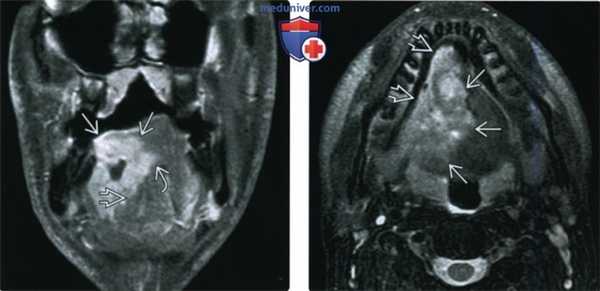

(Слева) При МРТ Т1ВИ С+ FS в корональной проекции в боковых отделах языка справа определяется большое объемное образование неправильной формы, накапливающее контраст во всех отделах за исключением центрального некроза. Опухоль вызывает инвазию подбородочно-язычной мышцы и пересекает среднюю линию.

(Справа) При МРТ Т2ВИ FS в аксиальной проекции, выполненной на уровне нижней стенки полости рта у этого же пациента, лучше видна зона опухолевой инфильтрации, распространяющаяся по направлению к нижней челюсти справа; тем не менее, признаки опухолевой инфильтрации костной ткани отсутствуют. Поскольку пациенту всего 31 год, была выполнена тотальная глоссэктомия и резекция нижней стенки полости рта, подтвердился ПКР T4aN2b (IVA стадия).